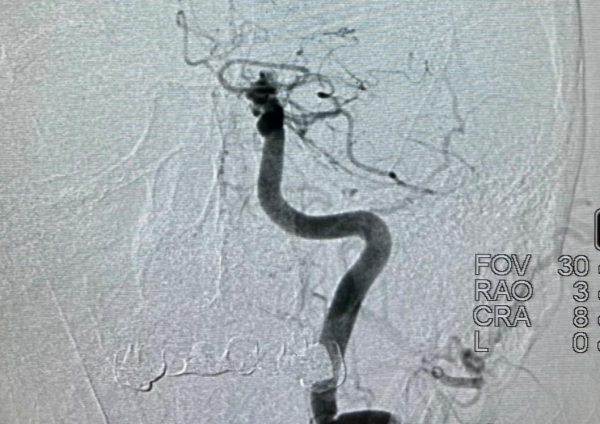

В ходе высокотехнологичной операции эндоваскулярный хирург больницы Андрей Прохорихин ангиографическим методом под контролем рентгена извлек тромб длиной четыре сантиметра из русла пораженного сосуда головного мозга.

Тромбоэкстракция подразумевает собой рентгенэндоваскулярное нейрохирургическое вмешательство. Оно заключается в удалении тромба из сосуда с помощью стента-ретривера через небольшой прокол в бедренной артерии.